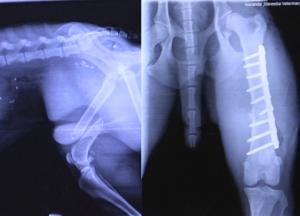

The healing process occurs much better in young animals versus the aged, who will need to be supported for a greater length of time before they gain their own strength. Stabilisation methods include casts, bandaging, external or internal pinning and bone plating. Sometimes more than one repair method is used on one injury. While casts may seem like an easy option, they do allow movement at the fracture site and the limb tends to move within the cast which is not ideal. The first four weeks of recovery are the most crucial to make sure the dog remains confined and unable to exert too much force on the broken bone. They will need to be led to go to the bathroom and not allowed to roam free. In most cases the dog should not resume normal work for around three months or longer but this needs to be assessed on a case by case basis with regular check-ups with your vet. For many fractures, some form of surgical repair will be necessary.

Internal fixation with bone plates and screws has become the most applicable fixation method for bone fractures over the last 50 years. They are applied to the outside of the bone and secured with screws through the walls of the bone. They are contoured to fit the bone and are available in many sizes and shapes to suits different bone fractures. They are able to counter both bending and rotational forces on the bone and can span areas where multiple fragments are present. In general, bone plating requires the least amount of aftercare, however all fractures need time to heal and patients will still need rest and controlled exercise to achieve the best healing. Pinning on the other hand may be the cheaper option but can lead to movement and rotation of the bones and prolong healing or possibly make the bones heal crooked. If you want the best outcome for your dog working wise and recovery time, plating is often the best choice but can be very expensive.